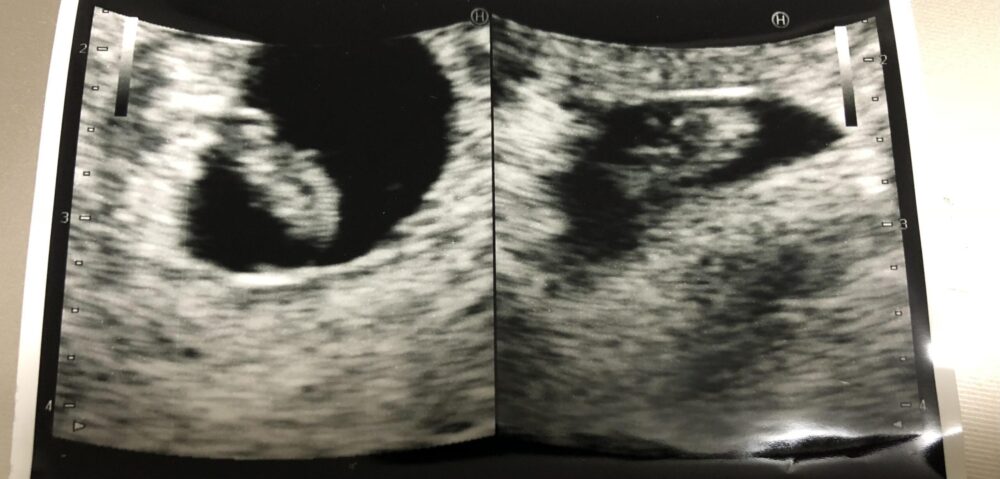

妊婦健診のエコー検査で、予期せぬ双子の妊娠が判明した瞬間を振り返ります。今回は、イノウエさんが体験した、不安と驚き、そして現実的な課題に直面したリアルな体験談をお届けします。

その日の妊婦健診、イノウエさんはエコー検査の時間がいつもより長いことに気づいていました。

「なんだかエコーの時間が長すぎるな…と思っていたんです」

不安を感じ始めた矢先、医師が漏らした「あれ?ああ〜〜………」という、何かをためらうような声。イノウエさんの心臓はドクンと跳ね上がります。

そして告げられた、双子の可能性。イノウエさんの口から出たのは、「えっ……???」という、ただ戸惑うばかりの言葉でした。喜びよりも先に、「どうしよう…?」という混乱した気持ちが心を占めていたと言います。